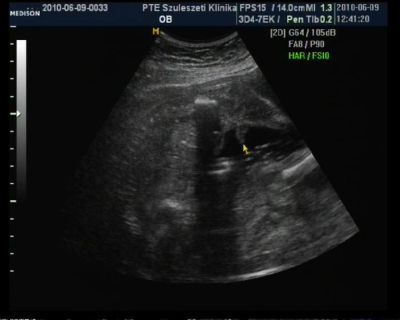

, aztán megnéztük a Törpöt. Készült róla egy nagyon jó kép, felteszem g-re.

BPD: 80,6 mm

THQ: 83 mm

becsült súly: 1750 g (jelzem, a doki megmondta a szórás: +/- 270 g, vagyis ennyire marha pontosak ezek a mérések!!!

)

vagyis tökéletesek vagyunk. Megint kortyolgatott a magzatvízből, és kiöltötte ránk a nyelvét, olyan édes volt.